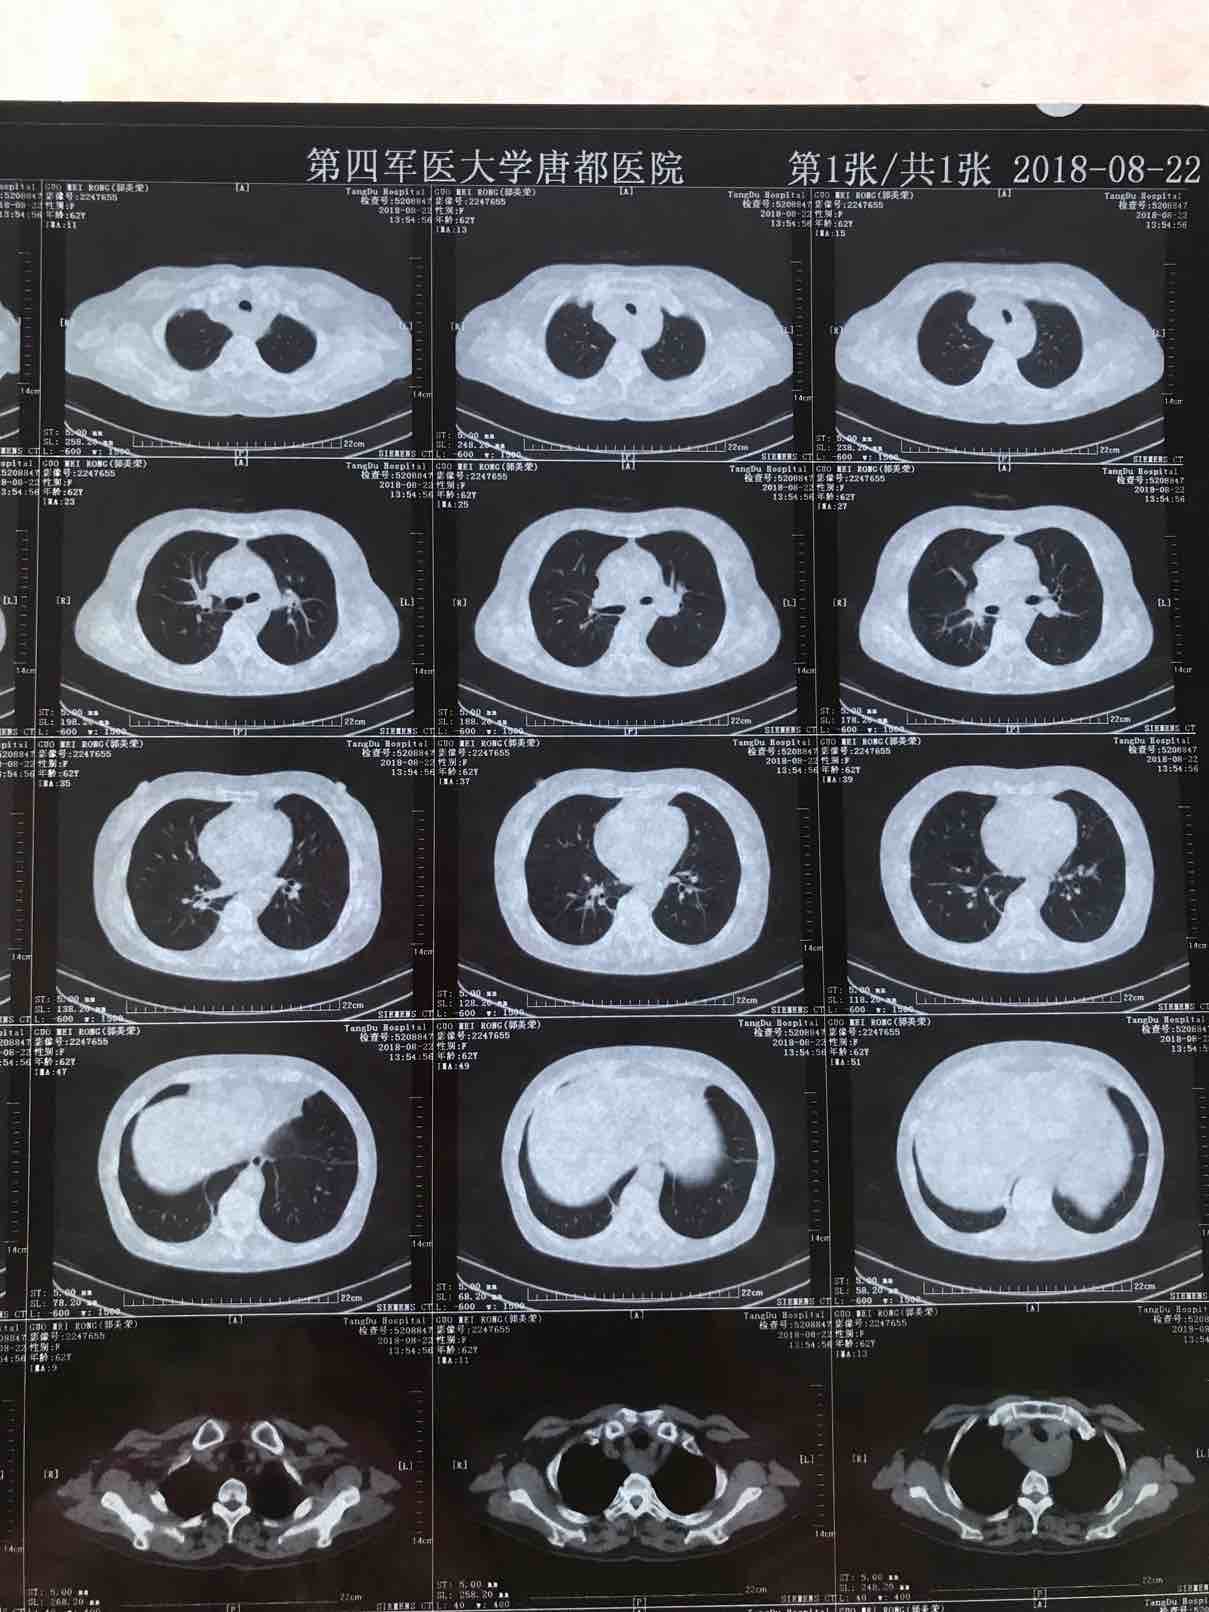

病历.患者,女,62岁,身高163,体重55公斤。2017年5月确诊肺腺癌晚期,胸膜转移,基因检测19突变,服用特罗凯至今。cea不敏感。近3个月体感变差,胸部牵扯痛,深呼吸痛,ca199从个位数升到74。周五复查发现进展了,如下图。

以下是8月的CT(1)

(2)

(3)